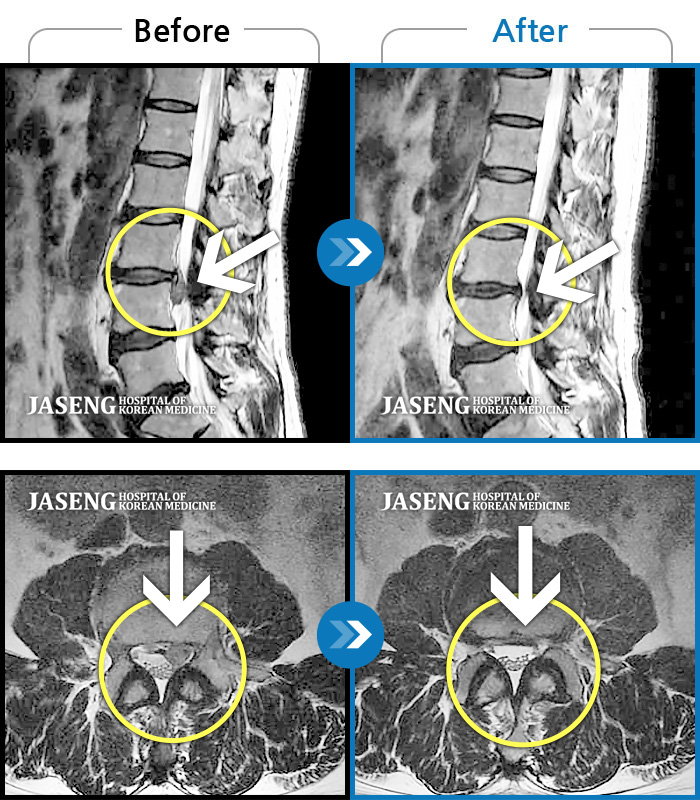

허리디스크

잠실 · 한상욱 원장

허리가 많이 아프고 왼쪽 다리가 저려 움직이기가 힘들다.

촬영시기

2022.01.19 ~ 2022.11.14

2022.12.02